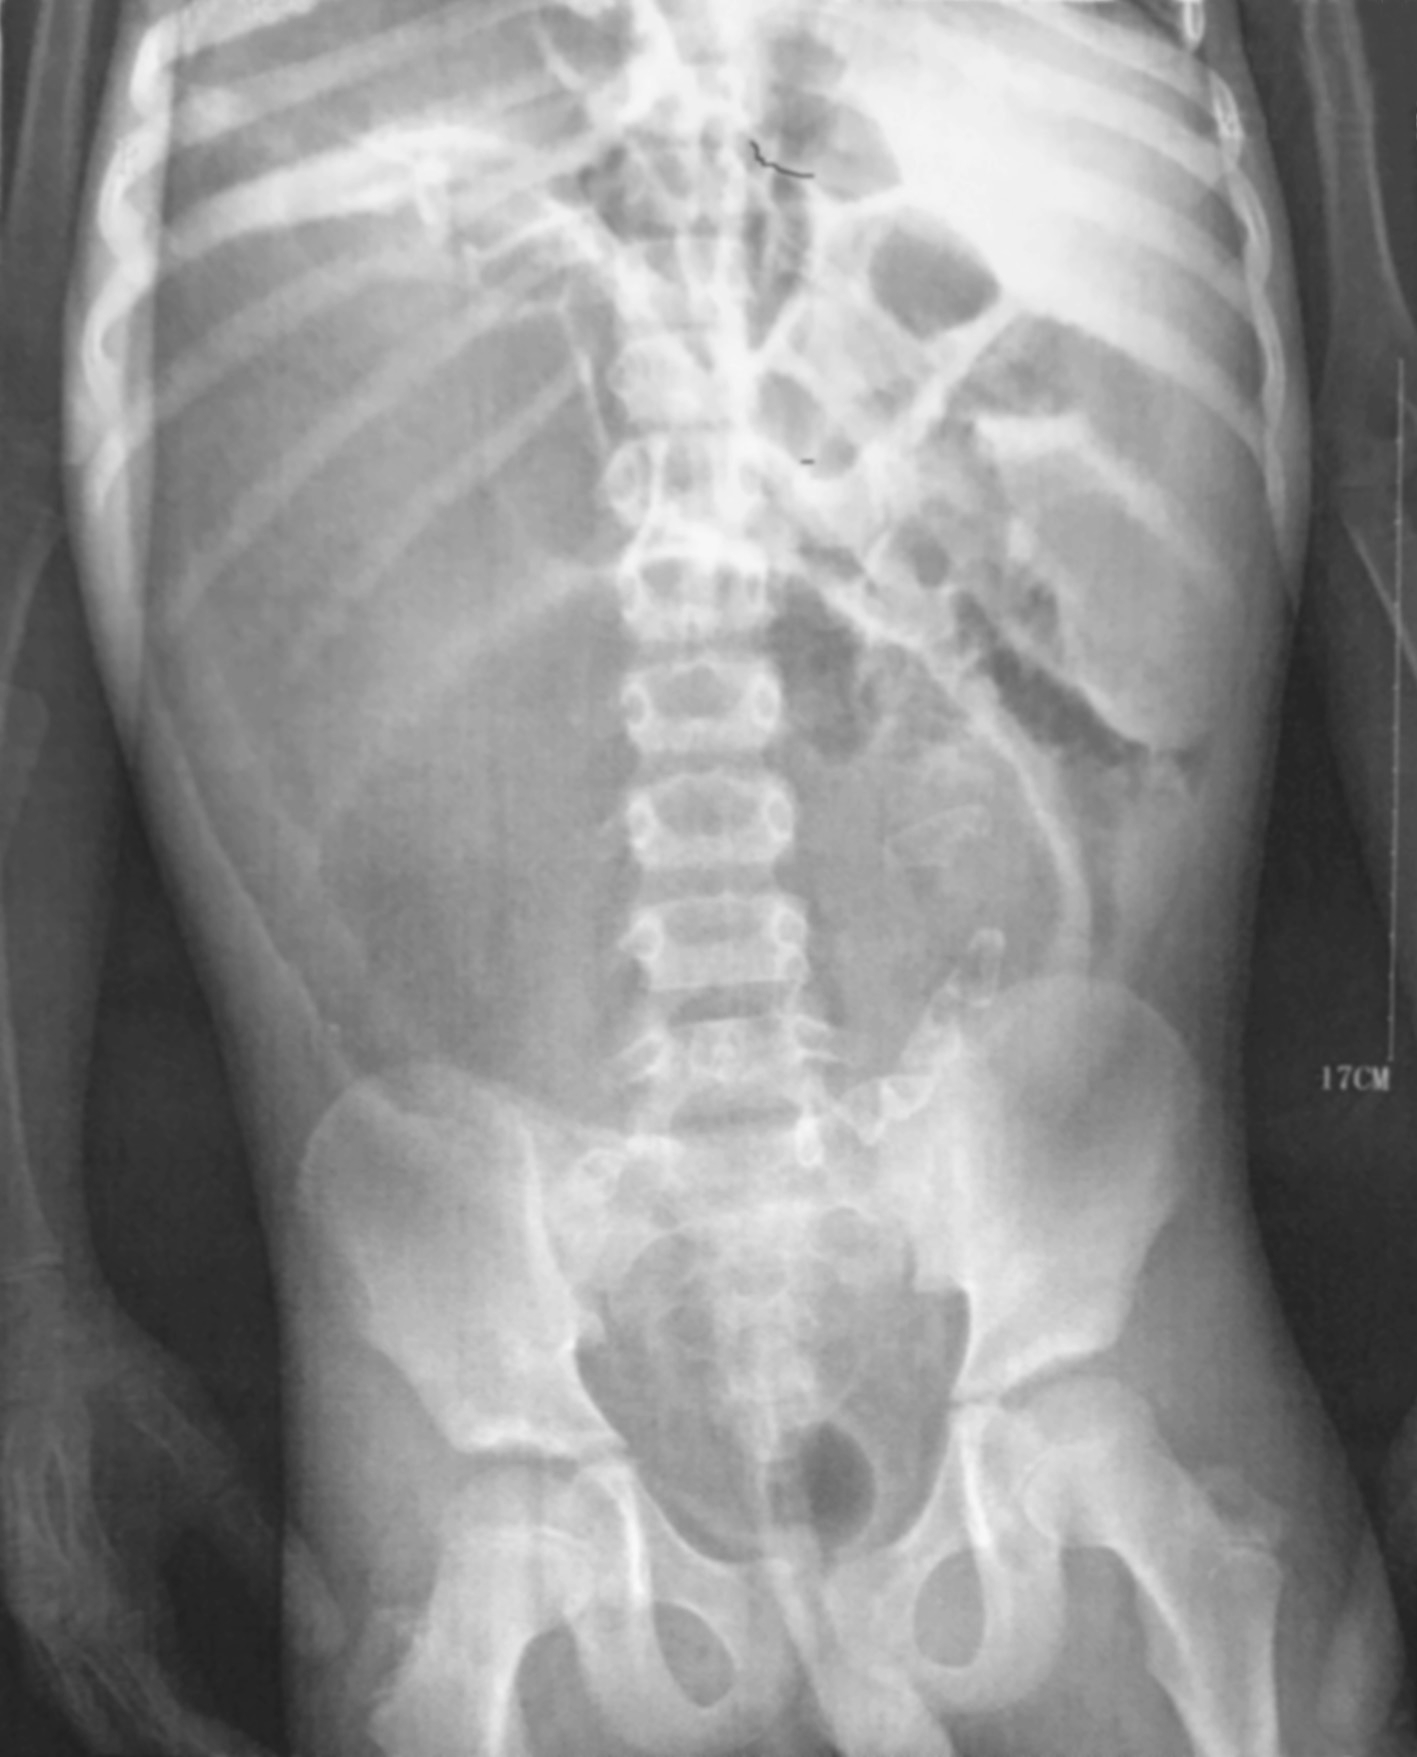

HD患儿立位腹部平片多表现为低位性肠梗阻,腹部可见多发液平、肠管积气、结肠扩张等。这种积气的肠段往往从盆腔开始,顺乙状结肠上行,而其远端则一直未见气体(图3-1)。新生儿时期结肠扩张不如儿童明显,单靠平片诊断比较困难,必须结合病史及其他检查(图3-2)。

图3-2 新生儿先天性巨结肠症腹部平片

肠管广泛积气,结肠扩张不典型。